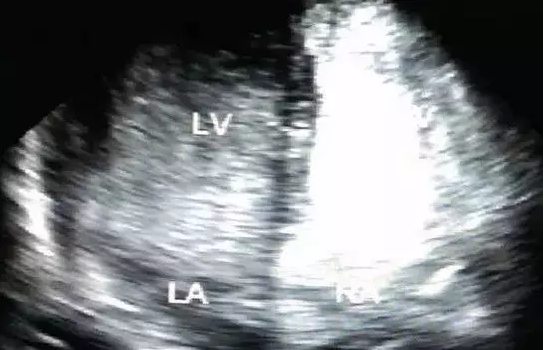

图2 经胸心脏超声右心“发泡实验”检查声学造影见大量泡从右心房向左心房分流